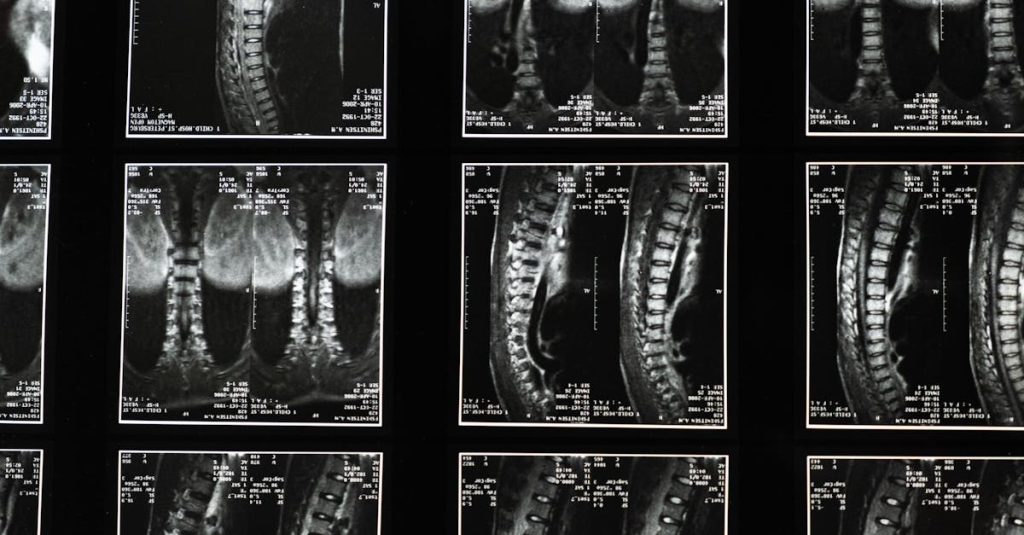

La sciatique est une condition caractérisée par une douleur qui se propage le long du nerf sciatique, du bas du dos jusqu’aux jambes. Cette affection résulte souvent d’une compression des racines nerveuses lombaires, ce qui provoque des douleurs intenses pouvant être invalidantes. Comprendre les facteurs contribuant à cette condition est essentiel, notamment le rôle du stress dans la gestion de la douleur.